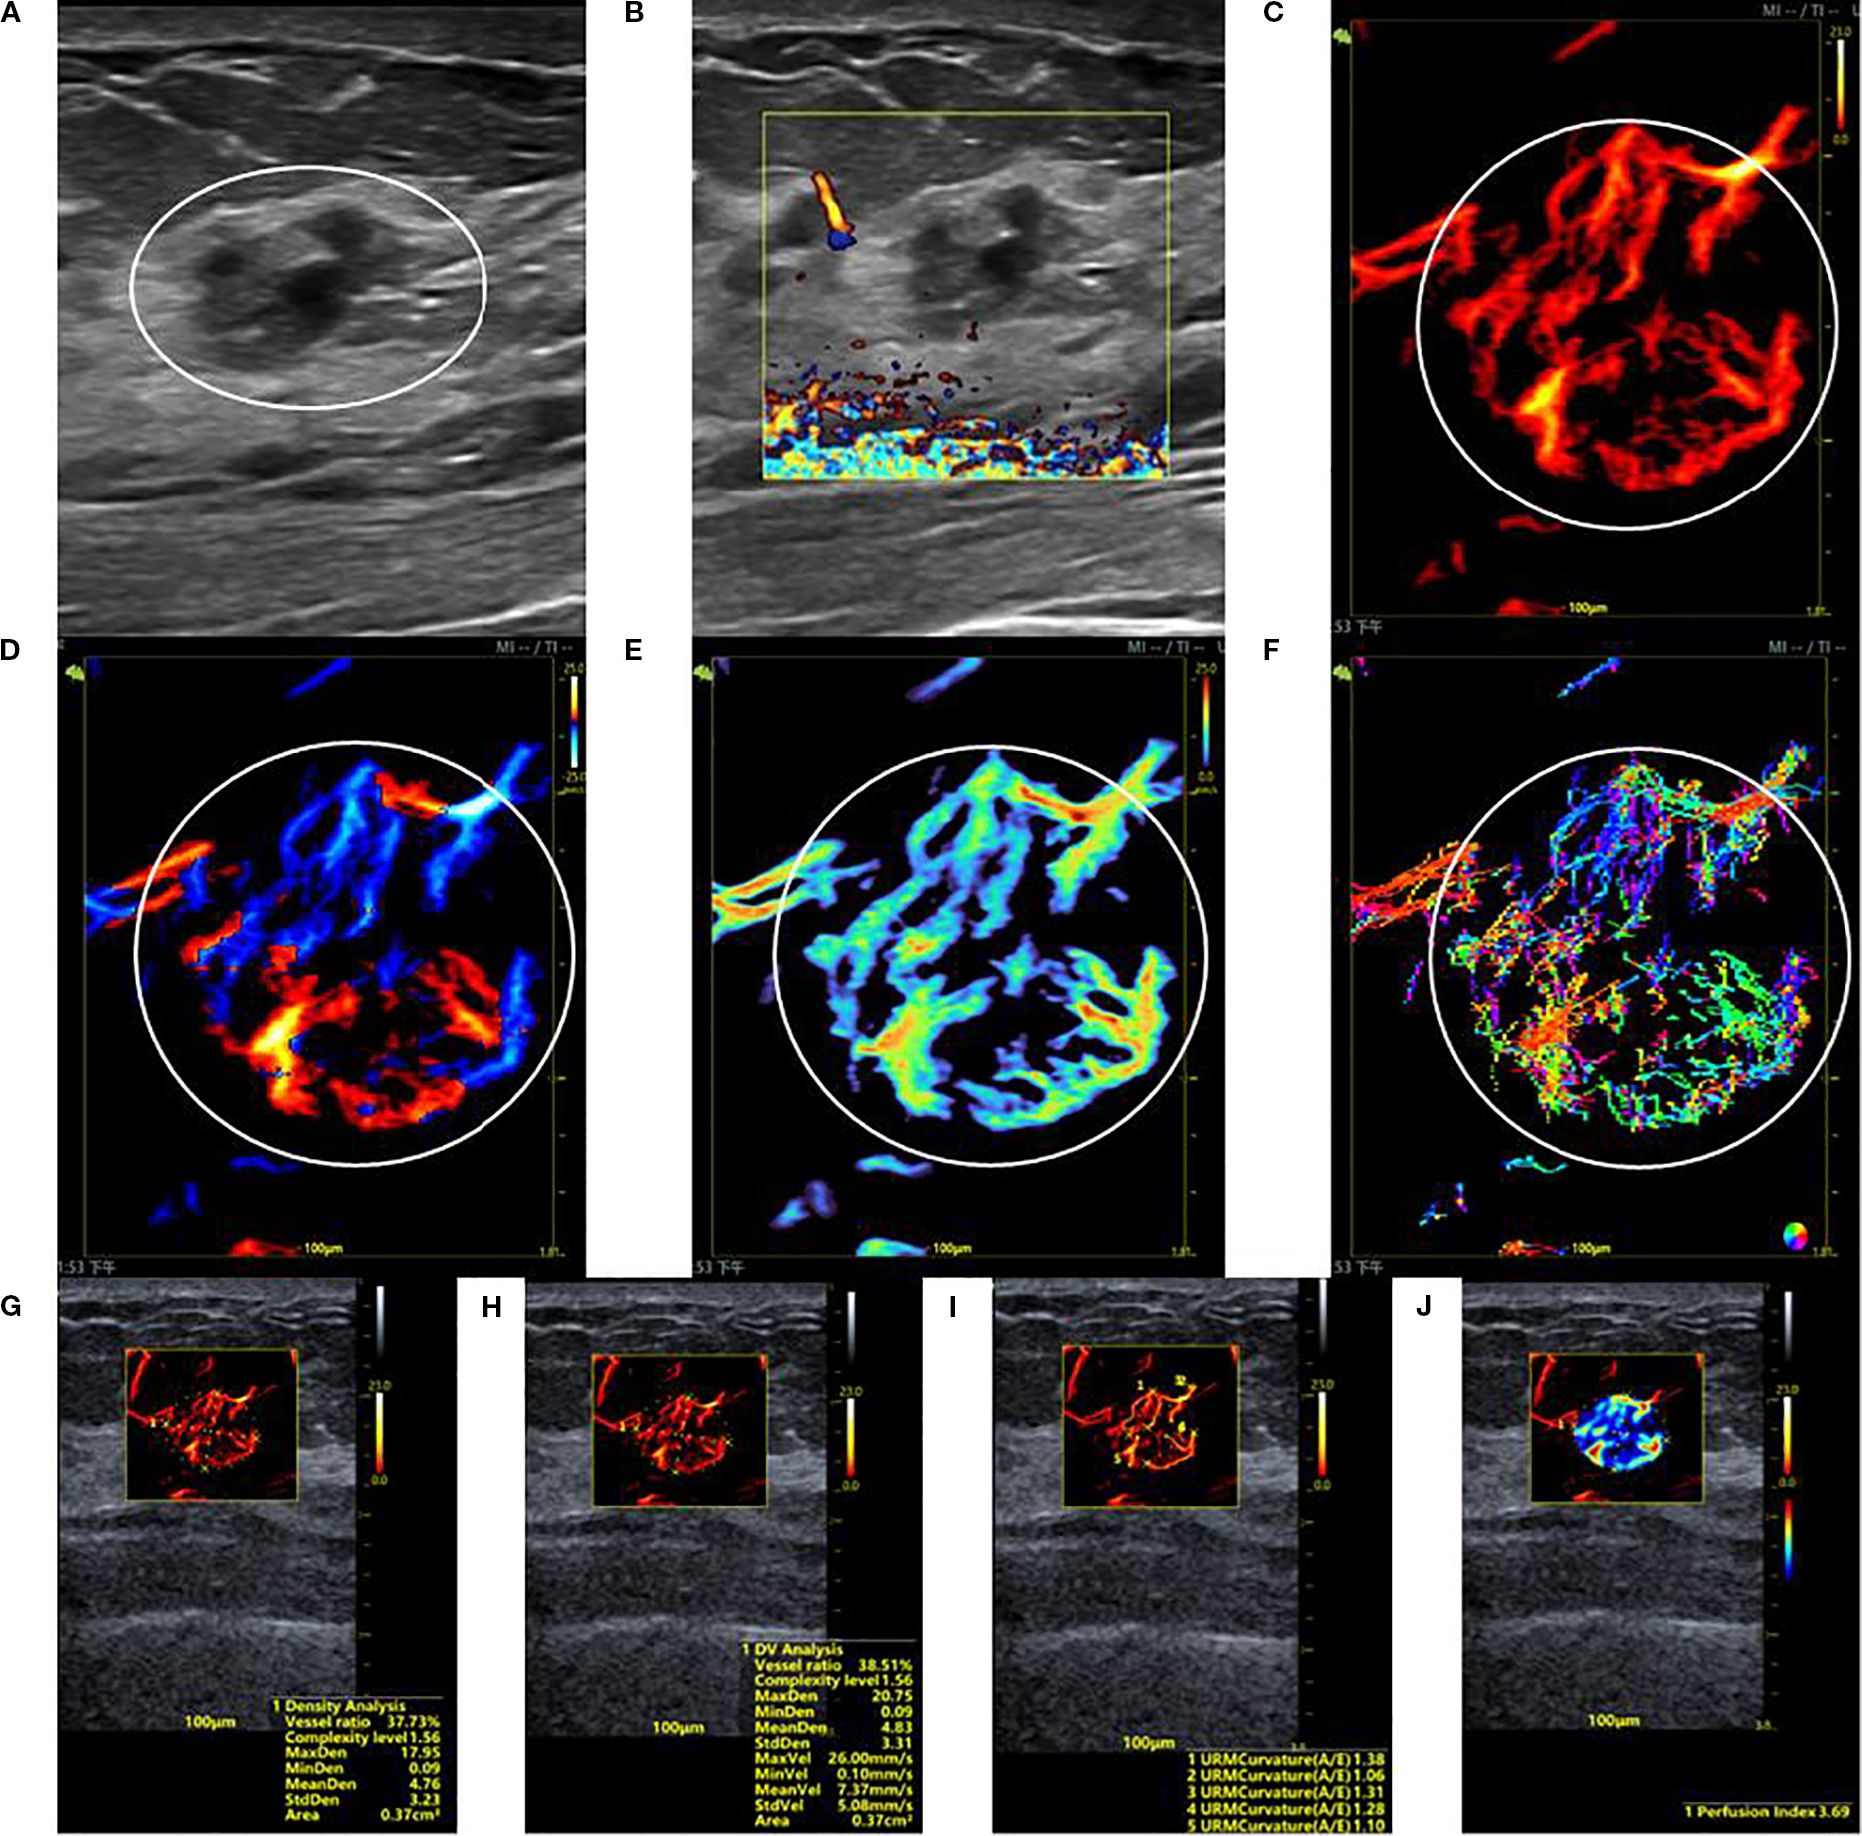

Figure 1. SRUS imaging of a malignant breast lesion: (A) Grayscale ultrasound findings suggest the presence of a hypoechoic mass (3.9 × 4.8 mm) with longitudinal orientation, ill-defined margins, irregular shape, heterogeneous internal echogenicity, angular edges, and multiple microcalcifications. (B) SMF image with Alder grade I classification. Density map (C), Orientation map (D), Velocity map (E), and Angle map (F), with the lesion region delineated by circular markers based on SRUS images and associated dynamic sequences. (G–J) SRUS parameter quantification panels: density ratio (49.75%), complexity level (1.60), maximum density (16.60), minimum density (0.07), mean density (5.06), maximum velocity (22.01 mm/s), minimum velocity (0.09 mm/s), mean velocity (6.91 mm/s), curvature A/E (1.26), and Perfusion Index (4.26).

Figure 2. SRUS imaging of a hypervascular benign breast lesion: (A) Grayscale ultrasound findings suggest the presence of a hypoechoic mass (15.2 × 10.0 mm) with parallel orientation, ill-defined margins, irregular shape, and heterogeneous internal echogenicity. (B) SMF image classified as Alder grade 0. Density map (C), Orientation map (D), Velocity map (E), and Angle map (F), with the lesion region delineated by circular markers based on SRUS images and associated dynamic sequences. (G–J) SRUS parameter quantification panels: density ratio (37.73%), complexity level (1.56), maximum density (17.95), minimum density (0.09), mean density (4.76), maximum velocity (26.00 mm/s), minimum velocity (0.10 mm/s), mean velocity (7.37 mm/s), curvature A/E (1.28), and Perfusion Index (3.69).